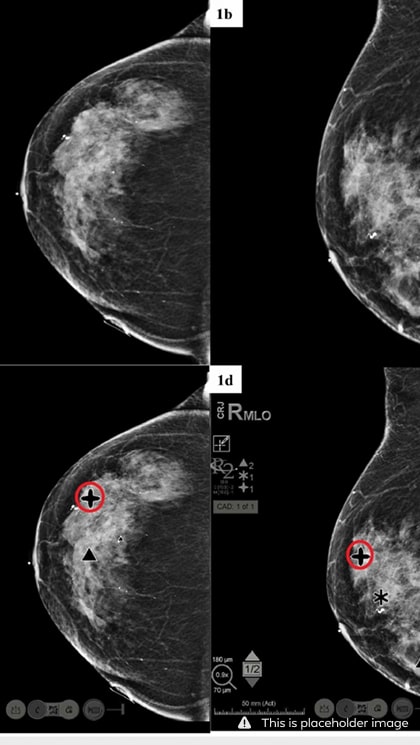

ImageChecker® 2D CAD analyzes conventional 2D mammography images to help detect potential breast cancer. When it comes to effectiveness, this system has shown an increased detection rate of breast cancer, and it’s particularly effective in women with dense breast tissue. The system is compatible with a variety of workstations and Hologic mammography machines, enabling a more timely diagnosis.

Hologic R2 CAD is one of the best mammography imaging systems available on the market. It uses advanced artificial intelligence or AI-based algorithms to analyze the imaging results, allowing it to recognize lesions and regions of significance in mere seconds. By highlighting potential abnormalities for further inspection by the radiologist, the R2 Cenova allows for much quicker detection and diagnosis.